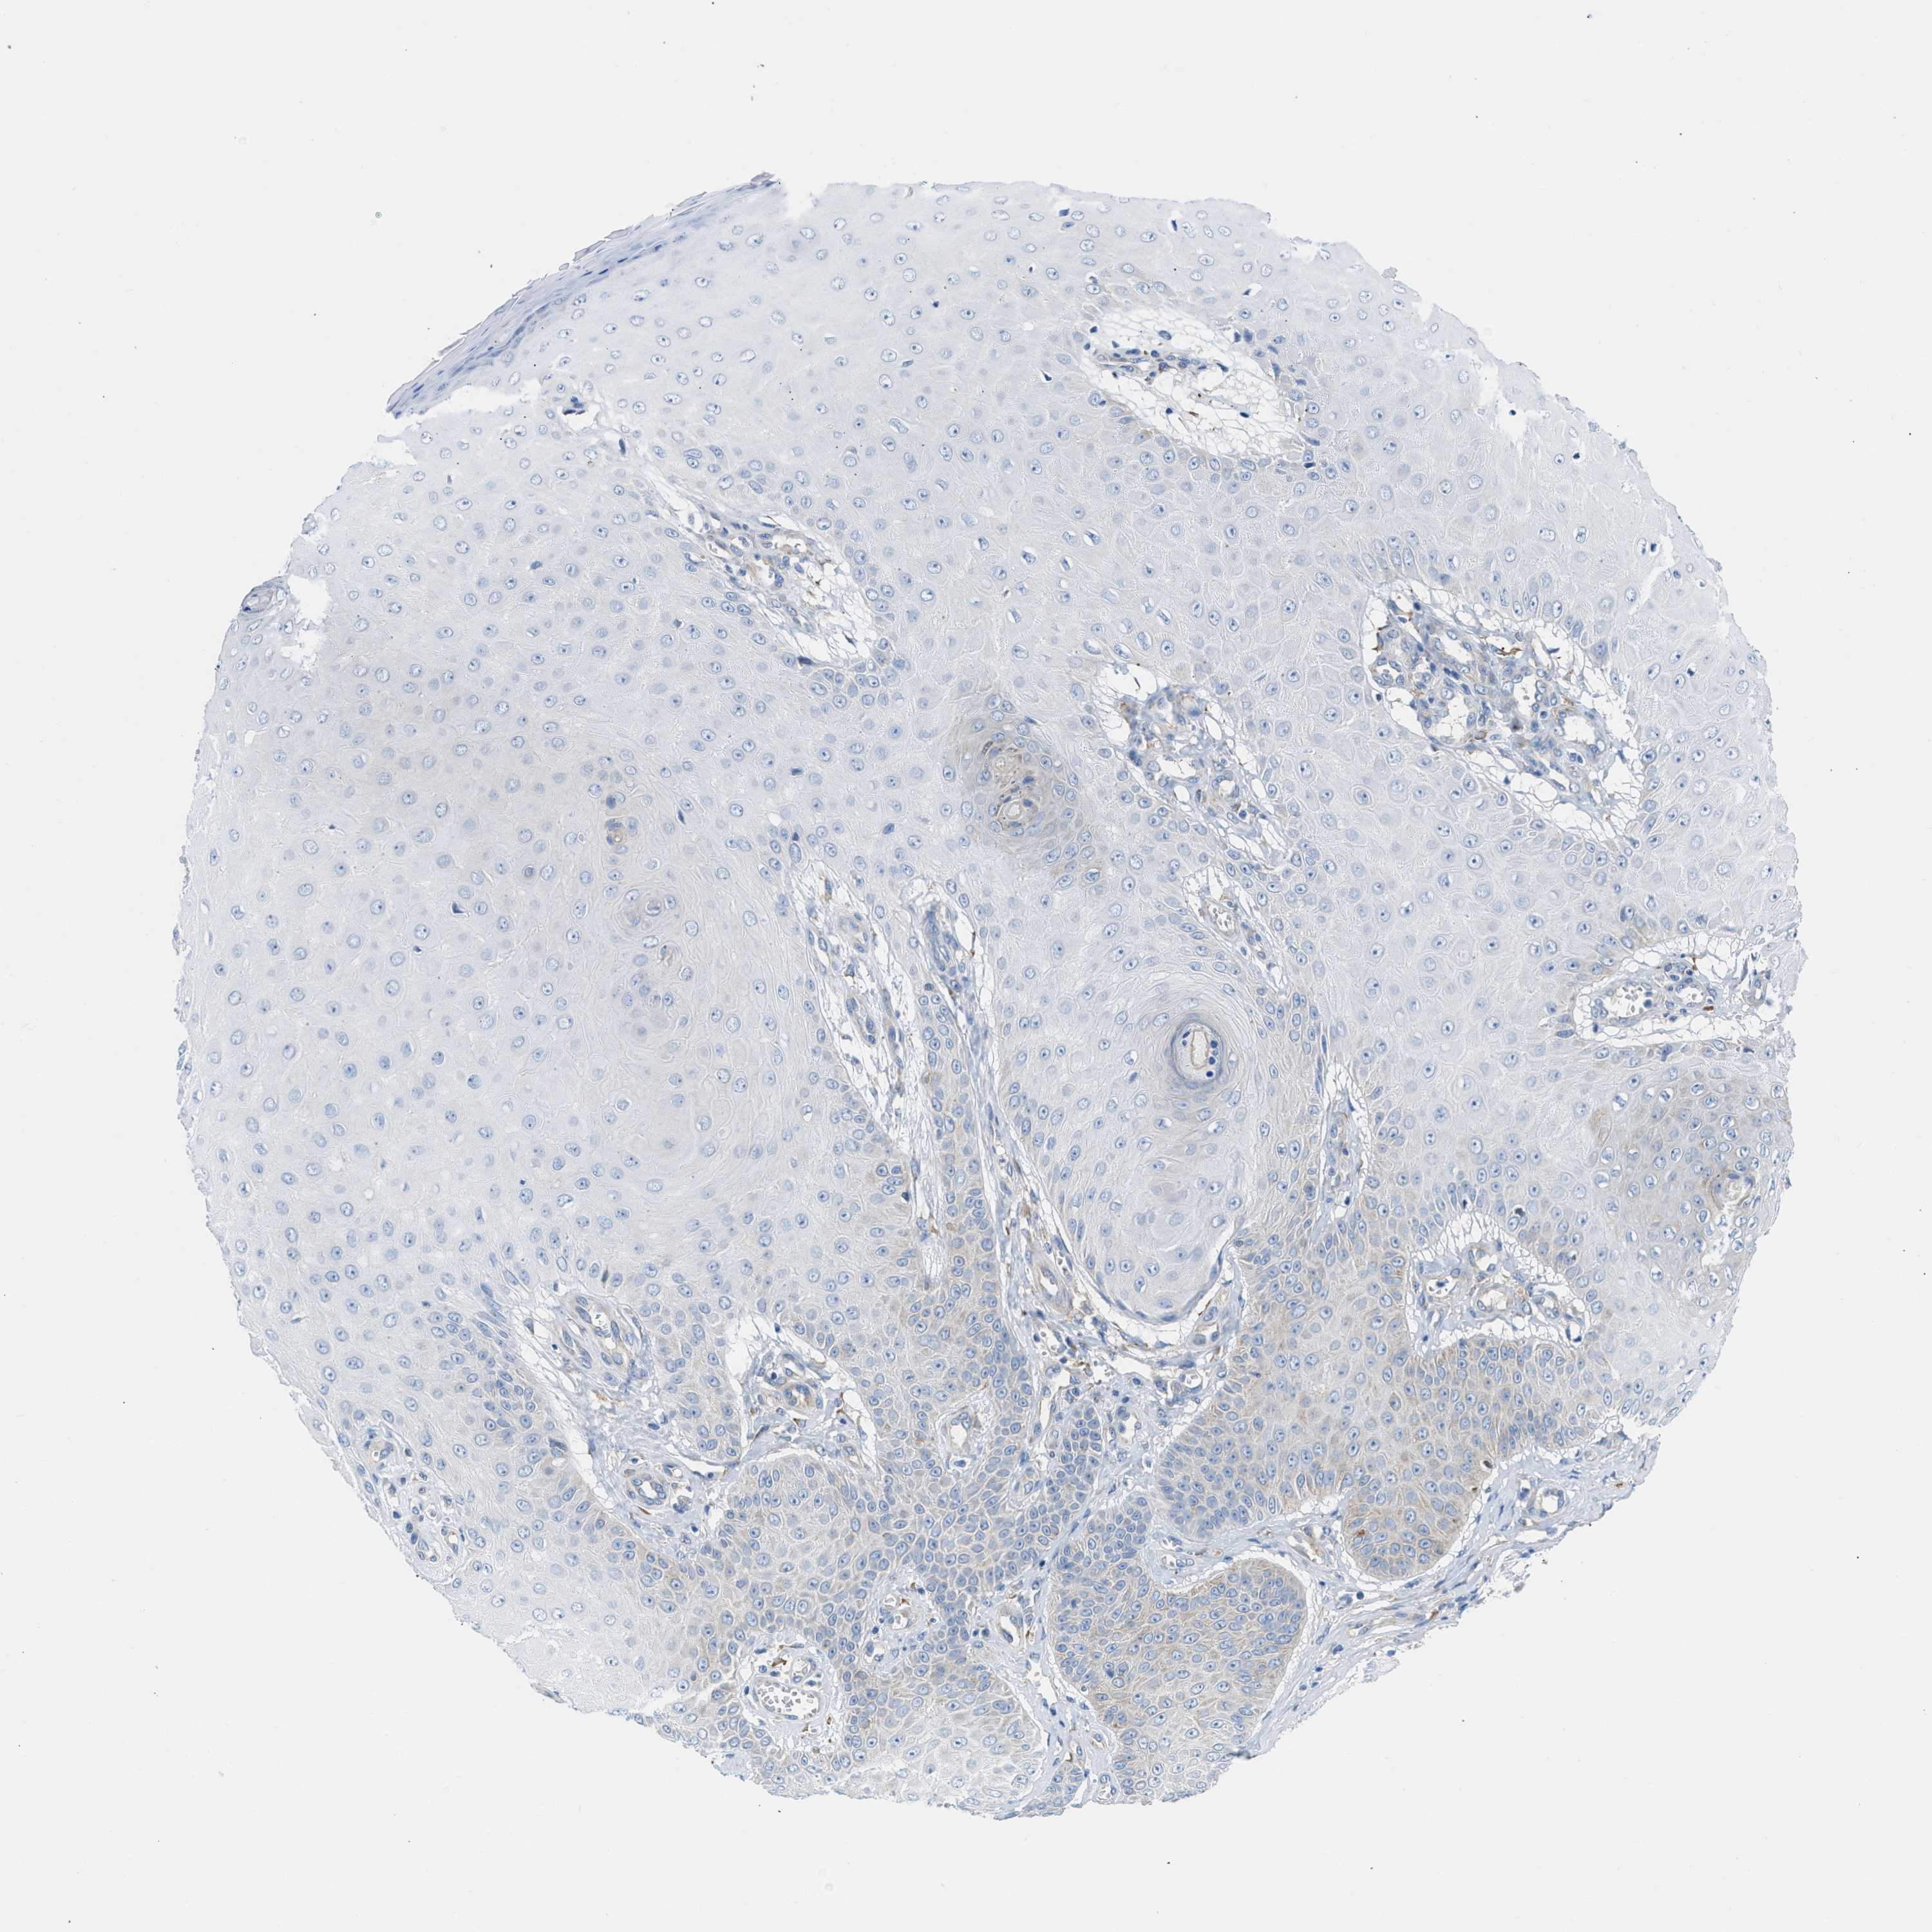

CANCER SKIN CANCER Show tissue menu

SKIN CANCER - Protein expressioni

A mouse-over function shows sample information and annotation data. Click on an image to view it in a full screen mode. Samples can be filtered based on level of antibody staining by selecting one or several of the following categories: high, medium, low and not detected. The assay and annotation is described here.

Each image is clickable and will lead to virtual microscopy that enables deeper exploration of all samples and also displays staining intensity scores, fraction scores and subcellular localization as well as patient and tissue information for each sample.

Antibody HPA018525

Staining

High

Medium

Low

Not detected

Intensity

Strong

Moderate

Weak

Negative

Quantity

>75%

75%-25%

<25%

None

Location

Nuclear

Cytoplasmic/membranous

Cytoplasmic/membranous,nuclear

Squamous cell carcinoma, NOS

Squamous cell carcinoma, metastatic, NOS

Basal cell carcinoma